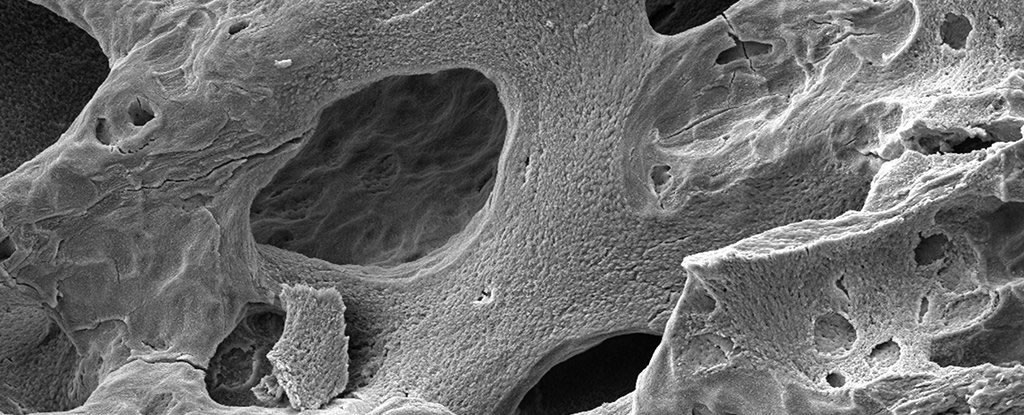

先前的研究指出,太空人在太空中每待一个月,因缺乏重力使得腿部压力不足,导致骨质密度下降1%到2%。

一项新研究扫描了17名太空人在国际太空站停留之前、期间和之后的手腕和脚踝的情况。加拿大卡尔加里大学、麦凯格骨骼和关节健康研究所所长、该研究的共同作者史蒂芬.波依德(Steven Boyd)说:太空人失去骨密度的量相当于在地球上生活几十年的流失量。